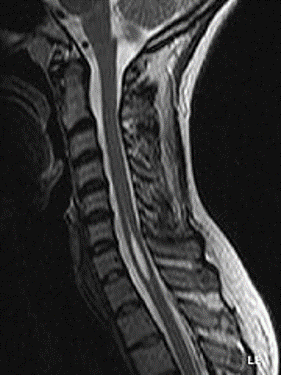

Die Syringomyelie ist eine seltene Rückenmarkserkrankung, bei der sich im Rückenmark (bevorzugt Hals- und Brustwirbelbereich) durch Liquorzirkulationsstörungen (Liquor=Gehirn-/Rückenmarksflüssigkeit) mit Flüssigkeit gefüllte Höhlen (Syrinx = gr. für Flöte, Plural: Syringen) bilden. Diese Höhlen verdrängen funktionsfähigen Nervenbahnen und Nervenzellen, so dass es zu neurologischen Funktionsausfällen kommen kann, die oft irreversibel sind. Die Größe der entstandenen Höhle steht in keiner Beziehung mit der Schwe-re der Erkrankung, sondern die Lage der Syrinx bestimmt die Symptomatik.

Viele im MRT gefundene Erweiterungen des Zentralkanals des Rückenmarks werden entsprechend vom Patienten selbst nicht bemerkt. Außerdem können Durchmesser und Längsausdehnung einer Syrinx von einem Tag auf den anderen schwanken. Nicht jede Syrinx im MRT diagnostizierte Syrinx wird im Laufe des Lebens auch symptomatisch. Allerdings kann auch eine noch kaum im MRT sichtbare Syrinx bereits heftige Beschwerden verursachen. Die Entstehung von Beschwerden ist von Lage und zeitlicher Entwicklung der Syrinx, aber auch von anderen Faktoren wie Schmerztoleranz des Körpers und Kombination mit anderen Erkrankungen abhängig.

Die Sicherung der Diagnose einer Syringomyelie erfolgt mit Hilfe der Kernspintomografie. Um zu verstehen, wie das Kernspintomogramm auch zur Aufdeckung der Ursache einer Syringomyelie beitragen kann, muss man die möglichen Entstehungsmechanismen der Syrinx näher betrachten.

Die Symptomatik der Syringomyelie ist vielfältig. Meist fällt die Krankheit zuerst durch Schmerzen/Kribbeln/Taubheitsgefühl im Bereich der Schultern und der Arme auf. Bei fortschreitender Erkrankung kommt es durch Schädigung der Leitungsbahnen für die Temperatur- und Schmerzempfindung zu Verletzungen und Verbrennungen, die der Patient selbst nicht fühlt. Auch die anderen Qualitäten der Sensibilität, wie die Berührungsempfindlichkeit oder die Tiefensensibilität (die anzeigt, in welcher Stellung sich der Körper oder die Gelenke befinden), können ein- oder beidseitig an Armen oder/und an den Beinen gestört sein. Störungen der Blasen- und Darmentleerung und sexuelle Funktionsstörungen sind ebenfalls möglich. Auch die Muskelaktivität kann gestört sein. Es kann zu Lähmungen oder spastischen Veränderungen, vornehmlich der oberen, aber auch der unteren Extremität kommen.

Reicht die Syrinx bis in die unteren Hirnanteile, kann es sogar zu Ausfallerscheinungen der Hirnnerven kommen. Weitere mögliche Folgeerkrankungen sind Fehlregulationen der Durchblutung, Schwindel oder Kraftlosigkeit. Die Haut kann bläulich und kühl erscheinen, später auch teigig geschwollen. Die Empfindungsstörungen tragen manchmal dazu bei, dass Wunden bei Syringomyelie-Patienten schlechter heilen und zu Komplikationen führen können.